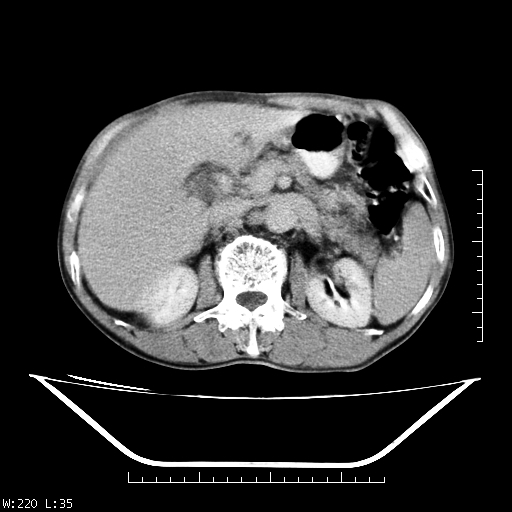

男,70,右上腹痛两月,有乙肝病史,b超提示肝占位,ct如下,请会诊。

补充:该患者afp9.24

肝右叶类圆型密度减低影,密度不均,边界清晰其内可见更低密度影,腹膜后可见小淋巴结肿大,增强扫描动脉期病灶明显强化,静脉期及延时扫描见强化不明显,快进快出表现。

1.肝右叶低密度影考虑为肝癌;

2.肝转移待除外。

平扫呈低密度占位,动脉期斑片状明显强化,病灶边缘清晰,见假包膜;门脉期呈低密度,符合肝癌快进快出强化特征

补充:该患者afp 9.24,似乎与原发性肝癌不符合,另胰头区结构正常吗?请大家继续发表高见。

平扫呈低密度占位,动脉期斑片状明显强化,病灶边缘清晰,见假包膜;门脉期呈低密度,符合肝癌快进快出强化特征,可能为纤维板型。建议介入治疗,效果会很好的。

快进快出   典型的原发性肝癌    肝门部见肿大淋巴结

肝癌,腹膜后淋巴转移不除外。